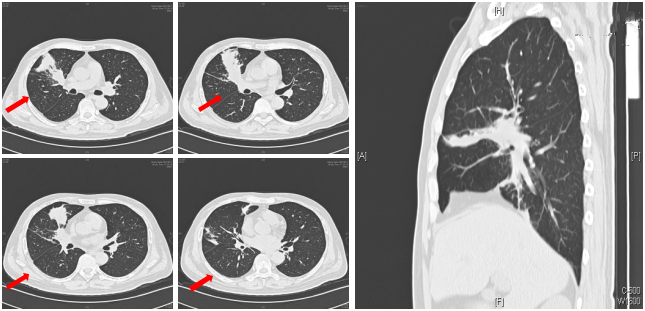

入院胸部CT可见右肺中叶和右肺下叶内基底段可见多发斑片和片状肺内渗出实变影(箭头所示)